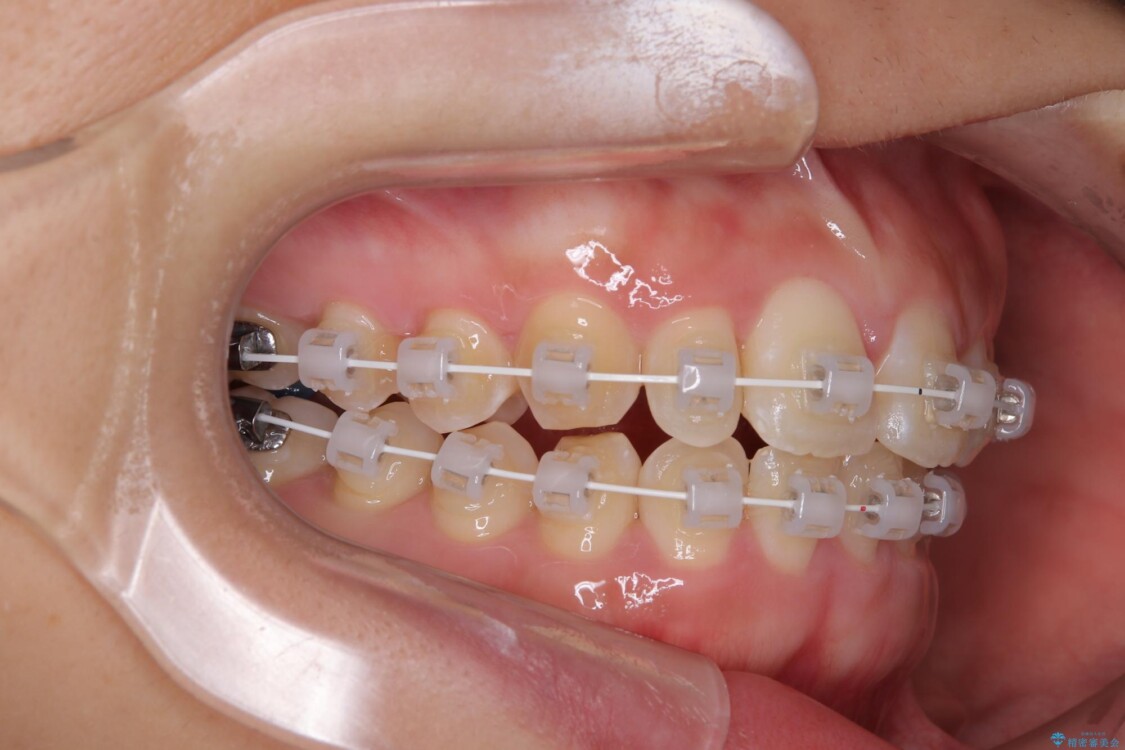

治療途中

• 目立ちにくい表側装置で1年完了!狭いアーチを側方拡大し前歯のデコボコを整えた症例 治療途中画像